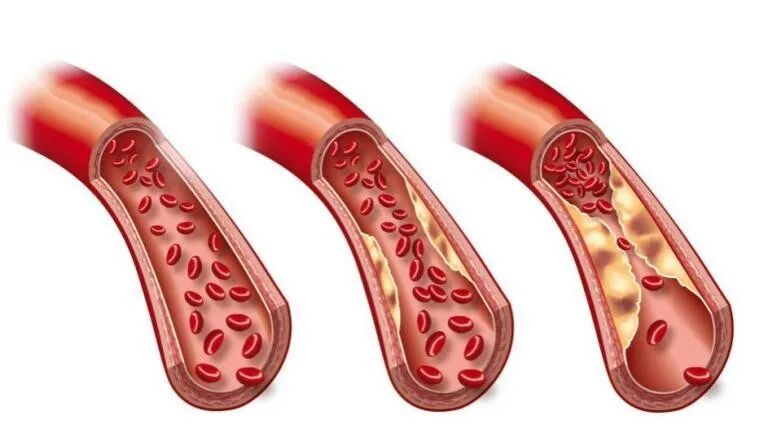

降血脂药能不能自行“续方”?这位阿姨的经历给所有人提了个醒

63岁的李阿姨(化名)周一上午早早就等在了诊室门口。一进门,她对坐诊的心内科主任医师周林丽说:“主任,...